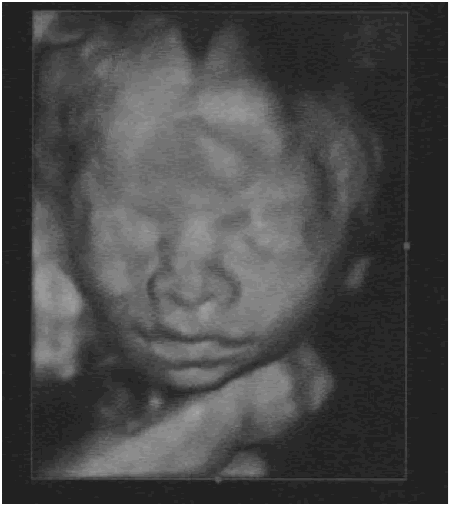

Cerise sur le gâteau, nous avons eu de superbes clichés des visages de Zoé et Timothée !

| Zoe a 24 semaines | Timothee a 24 semaines |